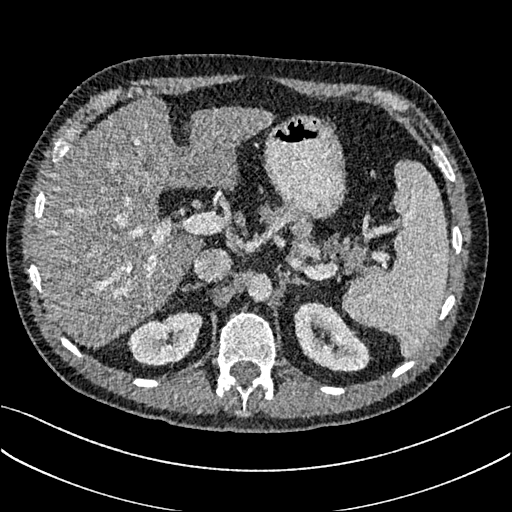

To demonstrate the effectiveness of the proposed network, we perform the qualitative comparisons over three representative abdominal images presented in Figs. 3, 5 and 7. For better evaluations of the image quality with different denoising models, zoomed regions-of-interest (ROIs) are marked by red rectangles and shown in Figs. 4, 6 and 8 respectively. Note that all results from different denoising models focus on two aspects: content restoration and noise-reduction. All CT images in axial view are displayed in the angiography window [-160, 240]HU.

The real NDCT images and corresponding LDCT images are presented in Figs. 3a and 3b. As observed, there are distinctions between ground truth (NDCT) images and LDCT images. Figs. 3a and 7a show the lesions/metastasis. Fig. 5a presents focal fatty sparing/focal fat. In Figs. 4a, 6a and 8a, these lesions can be clearly observed in NDCT images; in contrast, from Figs. 4b, 6b, and 8b, it can be seen that the original LDCT image is noisy, and lacks structural features for task-based clinical diagnosis. All adopted denoising models suppress noise to some extent.